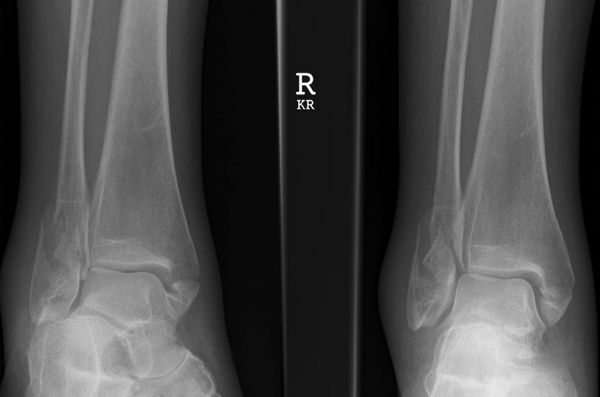

(3)Pott 骨折

内外踝骨折合并三角韧带断裂,踝关节完全失去稳定性并发生显著脱位者,称为 Pott 骨折。